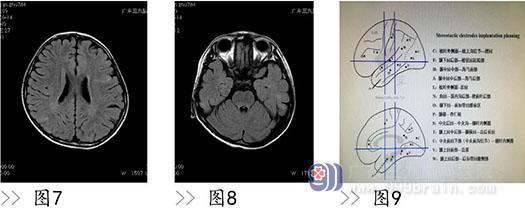

而在手术治疗方面,由于颅内结节病灶往往多个,皮层及皮层下、室管膜下均可累及,明确具体致痫灶是一个巨大挑战。必须指出的是 :虽然结节性硬化患者颅内结节往往较多,但并不是每一个结节都有内源性致痫性。在上世纪 90 年代,电极植入技术作为确定致痫灶的金标准被确定下来。如果经评价电极植入风险不高,患者经济情况允许,可疑致痫灶位于功能区需进行功能 Mapping,则电极植入后再手术应该是首选的策略。但是,由于相应的手术风险和较大花费,所有患者均行电极植入后再行切除性手术治疗并不太现实。术中皮层电极监测下剪裁式切除痫样放电区作为上世纪 90 年代前的标准,其核心是对刺激区的切除,有可能是一种扩大化的切除,虽然有一些缺点,比如麻醉药物的干扰,甚至误导致痫灶的范围,但是在麻醉科的良好配合及手术病人的合理选择下效果还是不错的。本组病人中 7 例患者因经济较困难,不能进行电极植入手术,但是在术中皮层电极监测下进行手术治疗其中 6 例也取得了不错的效果。我们的经验是无创性检查已有明确的脑区指向性,且相应脑区位于非功能区,该脑区的结节位于大脑凸面能够很好覆盖皮层电极进行术中监测的情况下,这种手术策略还是效果不错的。原则上,电极植入后明确致痫灶范围再进行手术切除的疗效应该优于术中皮层电极监测下的切除手术疗效。既往有基于电极植入后的研究证实结节病灶内是有致痫性的,也有研究认为致痫性位于结节病灶周围,还有研究认为结节病灶及其周边都有明确致痫性。本组病例中 3 例行 SEEG 监测,也证实致痫灶均大于皮层结节范围。因此在手术前,必须进行仔细的术前评估,包括详细的影像学检查,视频脑电图检查,症状学分析,必要时,应进一步行侵入性电极检查(图 7-11)。